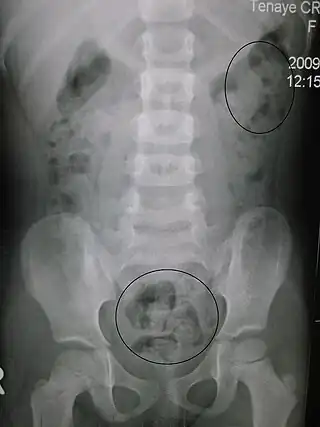

Estreñimiento visto a través de rayos X. Los círculos representan áreas de materia fecal (las heces están rodeadas de blanco debido al gas de los intestinos). | ||

Las radiografías del abdomen, por lo general solo se realizan si se sospecha obstrucción intestinal que puede revelar materia fecal retenida en el colon, y confirmar o descartar otras causas de síntomas similares.